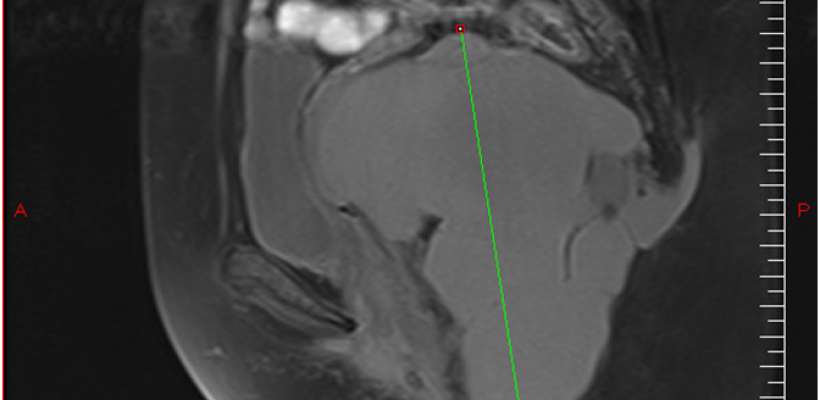

Le Scanner puis l’IRM (fig1) avaient montrer une masse retro rectale de 14 cm sur son grand axe d’allure kystique lobulée multiloculaire: déviant: rectum, vessie, utérus, vagin et allant jusqu’à l’aire Ischio anale à droite et en retro coccygien et qui serait un Hamartome ; La recto coloscopie montrait une compression extrinsèque du versant droit du rectum.

Figure1)IRM = Tumeur de 14 cm allant jusqu'a la région ischio anale et en retro-coccygien